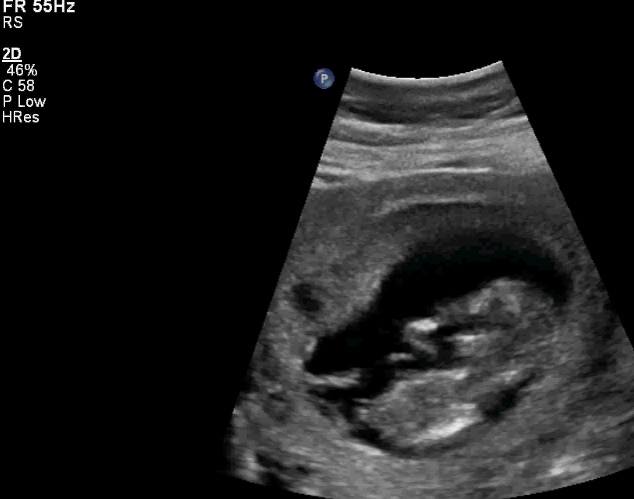

Hi ladies! This is an ultrasound from my friend that she had earlier today. Can you please give me your guess...boy/girl? Thank you!!

Here is another shot, but the spine is very curved so I know that can throw it off. This is a screen shot from a 2 second video. Attachment 21273

She is indeed a confirmed girl.